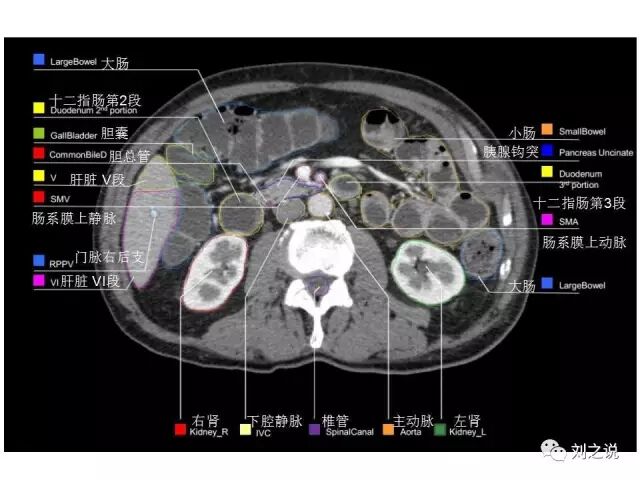

参考RTOG共识和3D-body解剖。

来源:刘之说